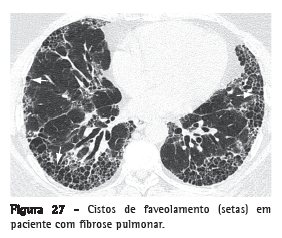

Faveolamento (favo de mel)

Cistos pulmonares criados pela destruição de espaços aéreos distais, por fibrose do parênquima pulmonar, com desarranjo da arquitetura de ácinos e bronquíolos. Os cistos de faveolamento são revestidos por epitélio bronquiolar metaplásico e representam o estágio terminal de várias doenças pulmonares.(1,48) Na TCAR, caracteriza-se por múltiplos cistos, em geral de localização subpleural, com diâmetros semelhantes (tipicamente de 0,3-1 cm), agrupados em camadas e compartilhando

paredes bem definidas de 1-3 mm de espessura (Figura 27).(49)

Representa um marcador tomográfico de fibrose pulmonar. As causas principais incluem fibrose pulmonar idiopática, colagenoses, pneumonite por hipersensibilidade crônica, reações pulmonares medicamentosas e asbestose.(28) Deve ser diferenciado de enfisema parasseptal e de bronquiolectasia de tração.